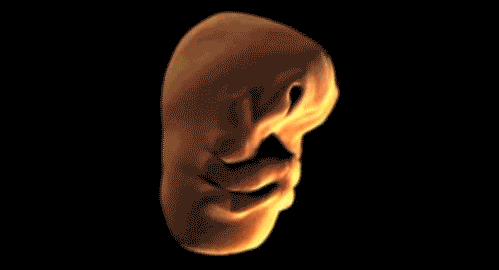

▼21. 人类胚胎发育的过程,你知道自己是怎样来到这世界上的吗?